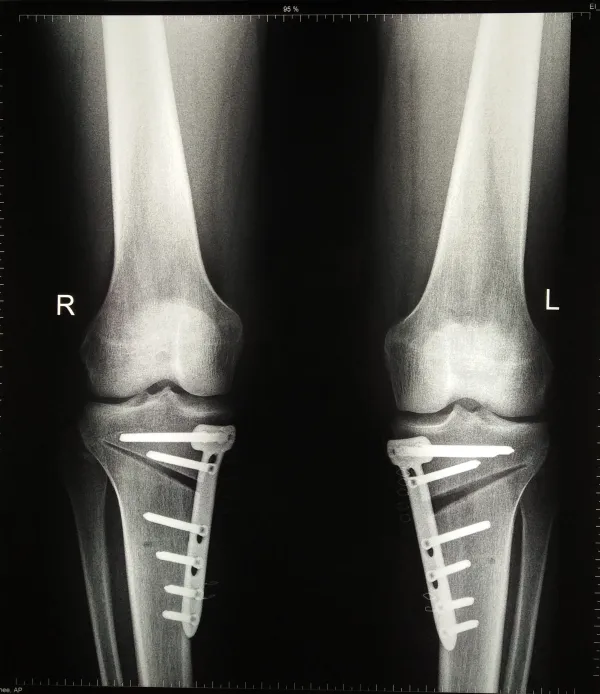

2. الأشعة السينية

تُستخدم لتحديد درجة التقوس ومعرفة ما إذا كانت المشكلة في العظم أم في صفيحة النمو.

• جراحة قطع العظم (Osteotomy):

• تستخدم هذه الجراحة في الحالات الأكثر تعقيدًا، خاصة عندما لا يكون هناك نمو كافي في العظام لتطبيق النمو الموجه، حيث تتضمن العملية قطع العظم المنحني وإعادة وضعه في الاتجاه الصحيح، ثم تثبيته باستخدام صفائح ومسامير داخلية أو إطار خارجي، ورغم كونها أكثر تدخلاً، إلا أنها فعالة في تصحيح التشوه واستعادة التوازن في الساقين.